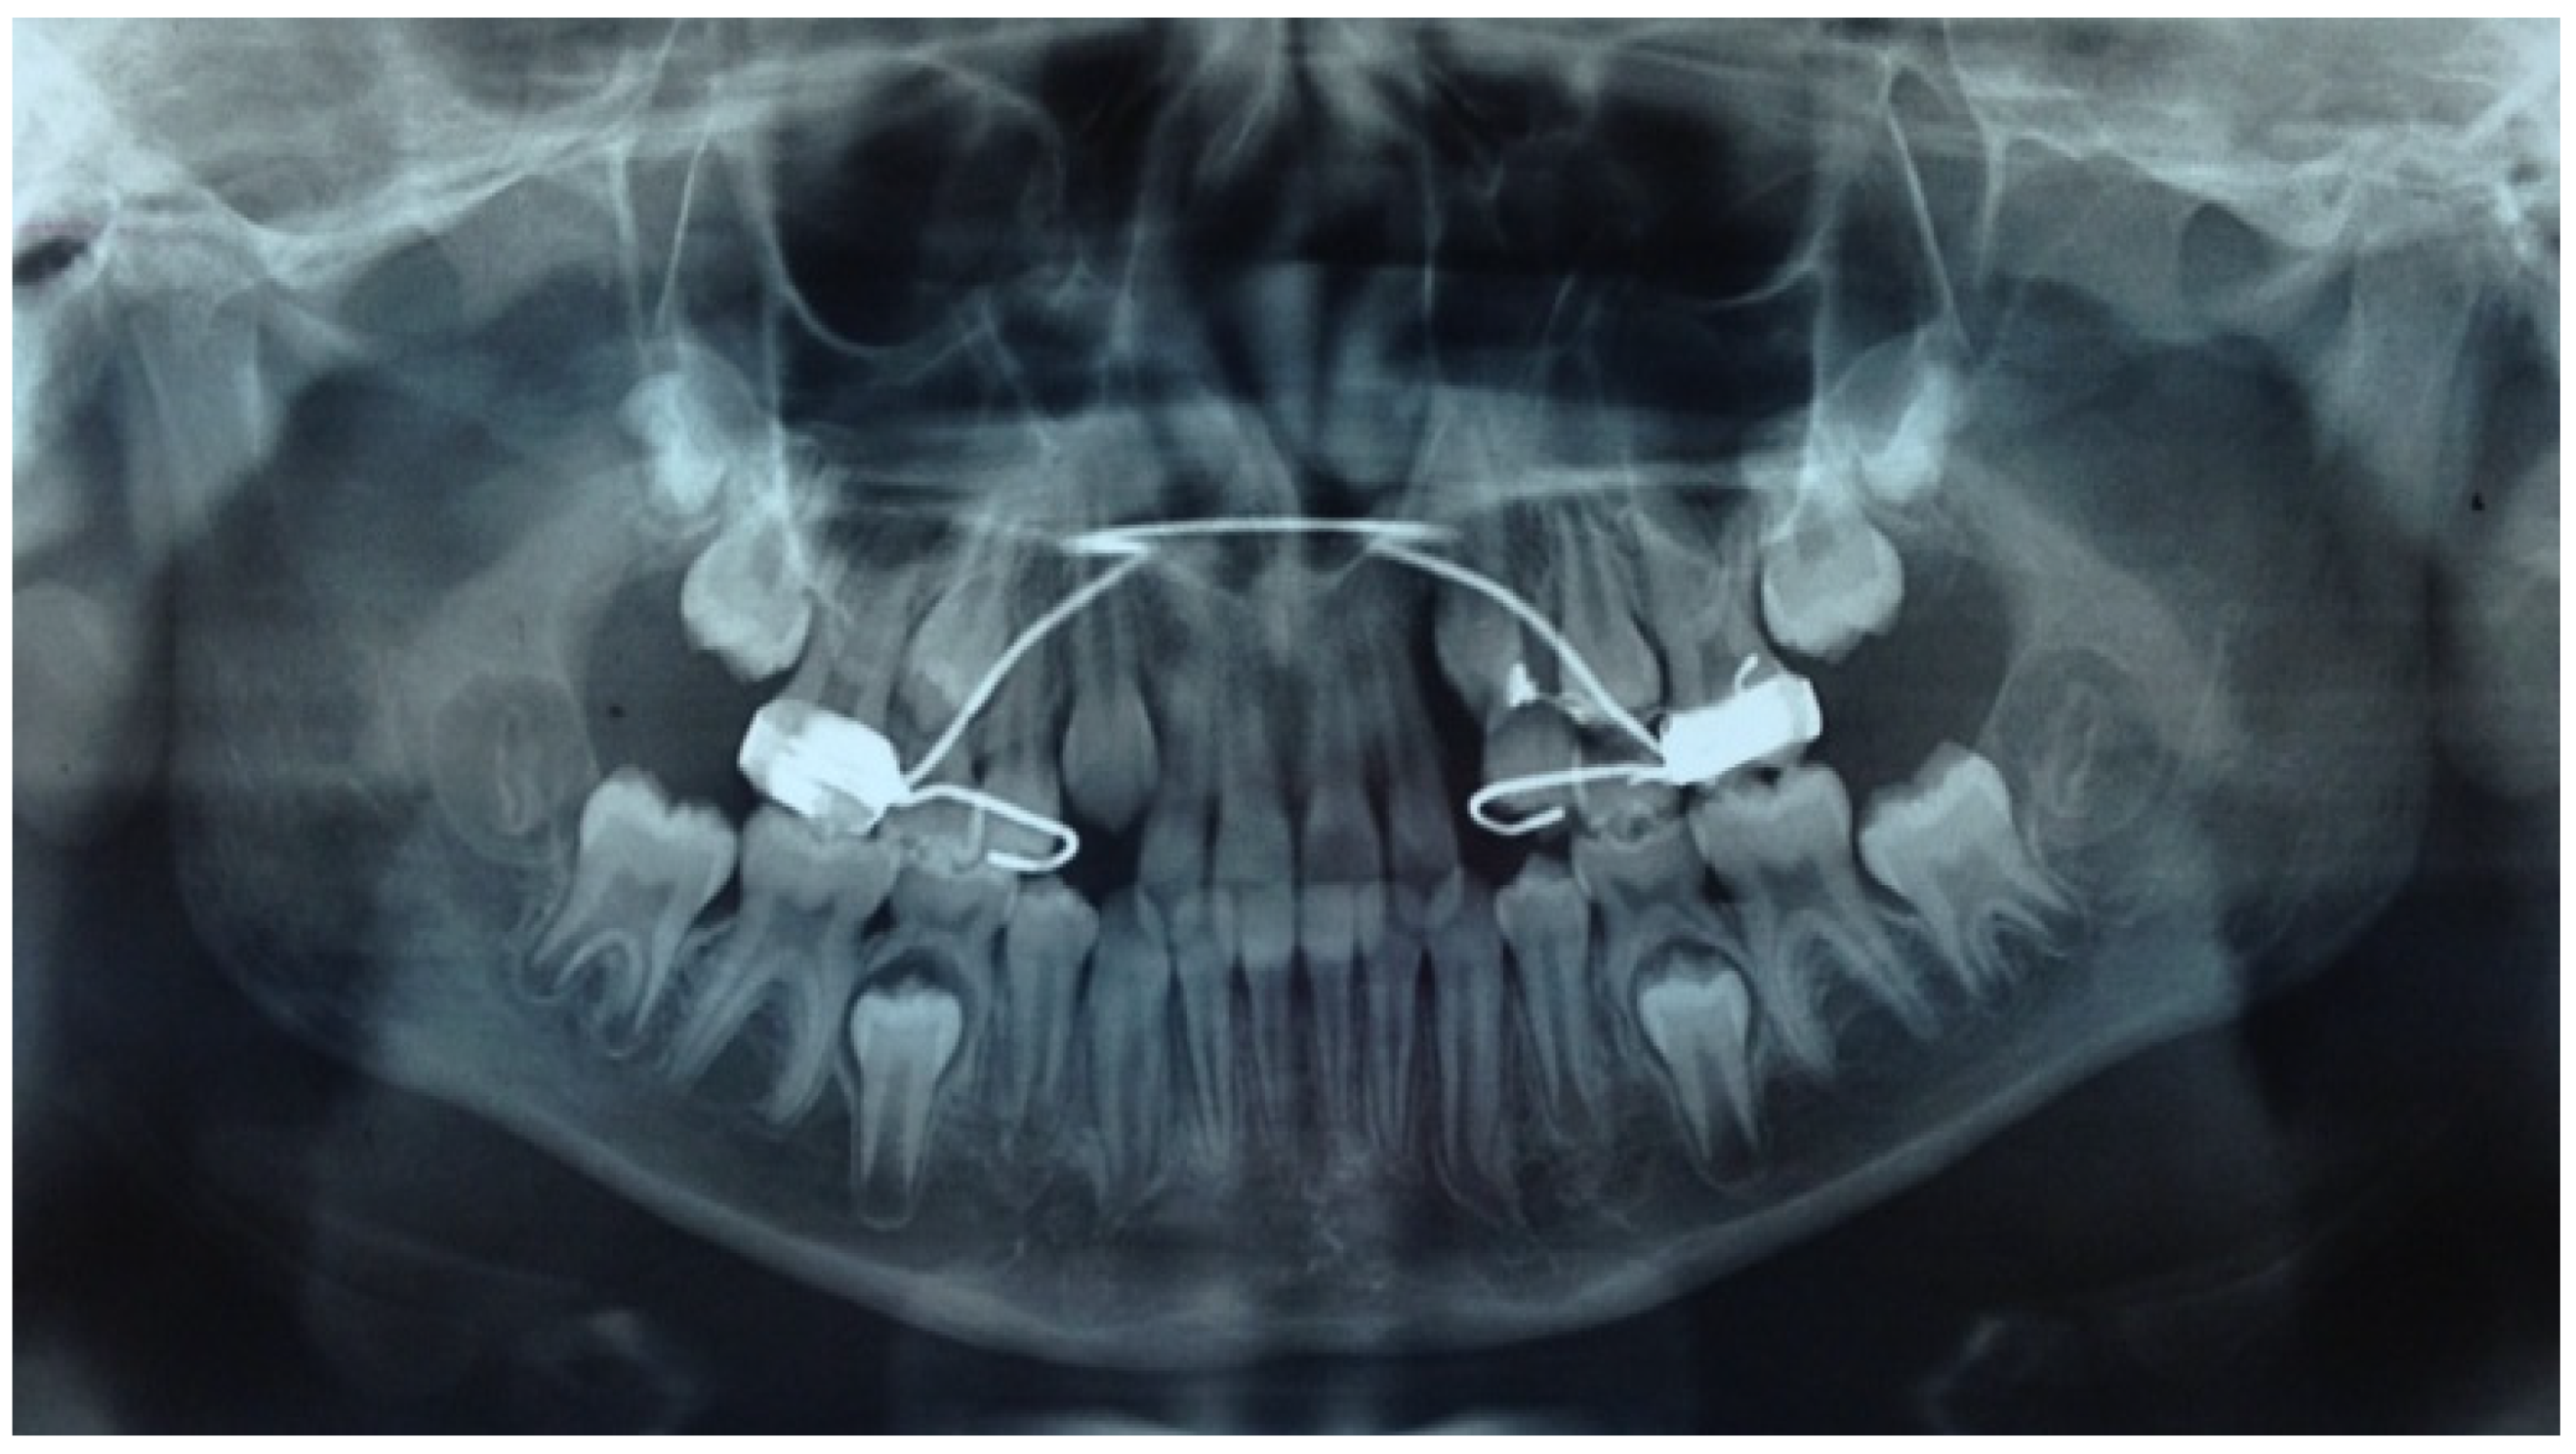

- In the first step, a panoramic radiograph and a teleradiography of the skull in latero-lateral projection is required. The observation of the panoramic radiography should show the position of the impacted canine, evaluating the relationships of the canine crown with the roots of the adjacent teeth, the alpha angle, and the distance of the impacted tooth from the occlusal plane. The cephalometric study of the teleradiography should provide information about the eventually present malocclusion and treatment needed;

- A cone beam CT, eventually limited to the sector of the impacted tooth, is mandatory to evaluate the three-dimensional relationships of the teeth with the adjacent structures and all of the conditions eventually limiting the correct insertion of temporary anchoring devices (TADs) such as anatomical variation of the lateral extension of the maxillary sinus, the availability of correct inter-root space, or the presence of the premolars buds in mixed dentition. The use of a tridimensional imaging is justified from the need of an accurate assessment of the position of the impacted canine and of its relation with the adjacent structures, due to the higher spatial resolution obtained with lower radiation dose [15].

- The correct site of miniscrew insertion is previously established by means of cone beam CT images, and it is usually planned in the inter-radicular area between the second premolar and the first molar;